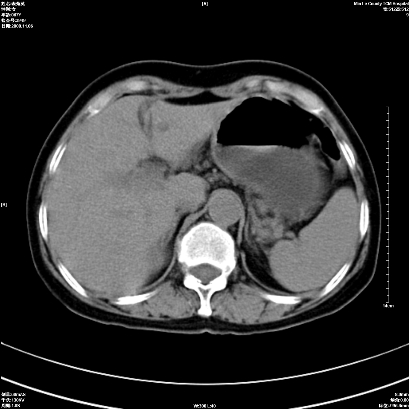

以下是引用卜一在2008-11-6 15:58:00的发言:[br]胰头略增大,胆总管扩张,末端渐行性狭窄。多考虑:胰头癌!建议增强!